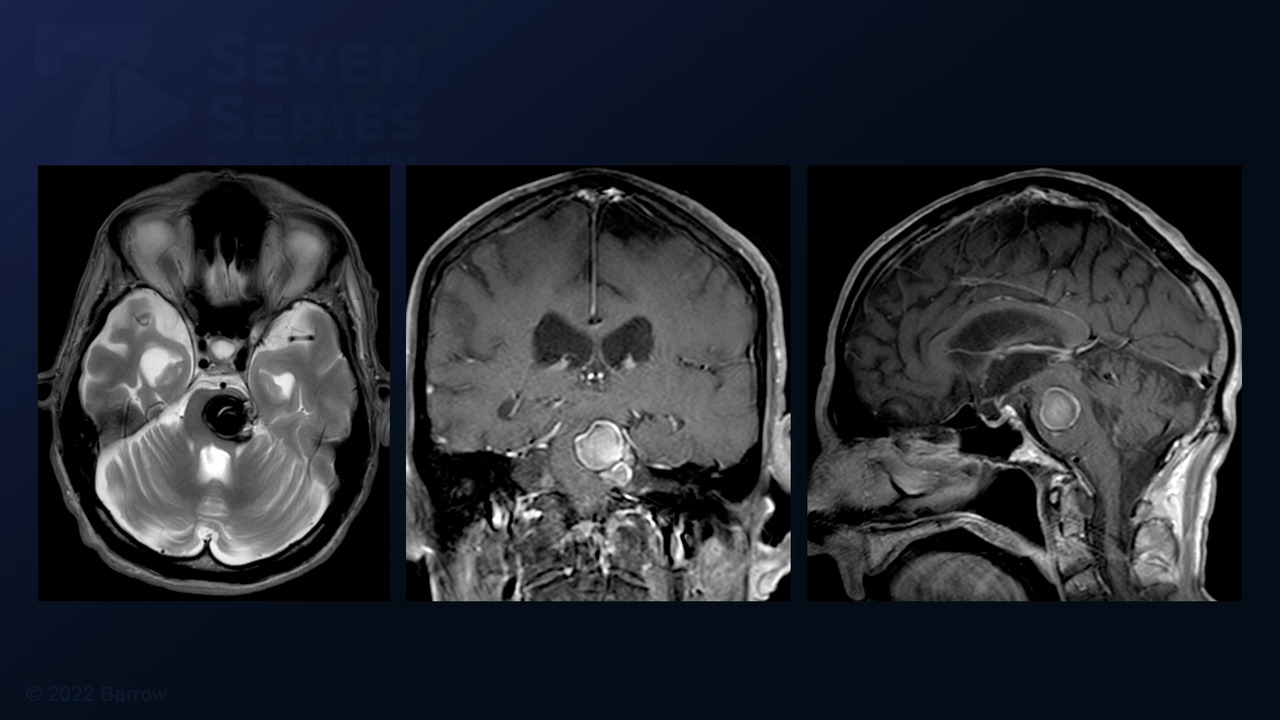

#77: Retrosigmoid Craniotomy and Resection of a Peritrigeminal Pontine Cavernous Malformation

Episode 77 of Seven Series shows a retrosigmoid craniotomy and resection of a peritrigeminal pontine cavernous malformation.